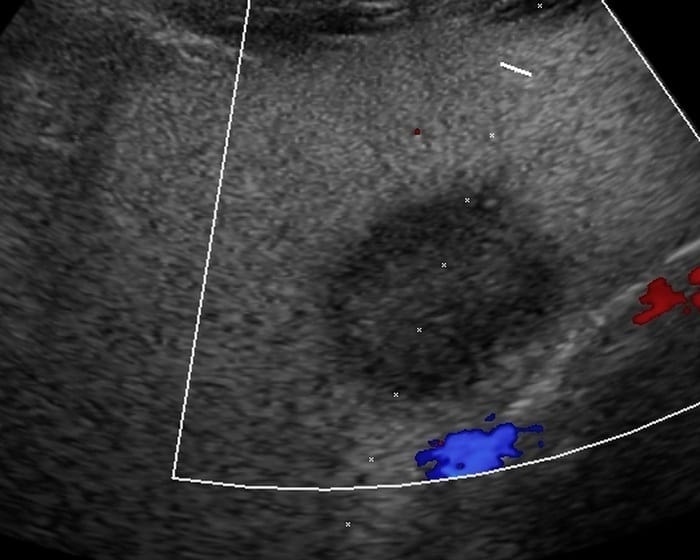

Ung thư đường mật

» Thông tin: Nam giới – 57 tuổi.

» Lâm sàng: Đau bụng.